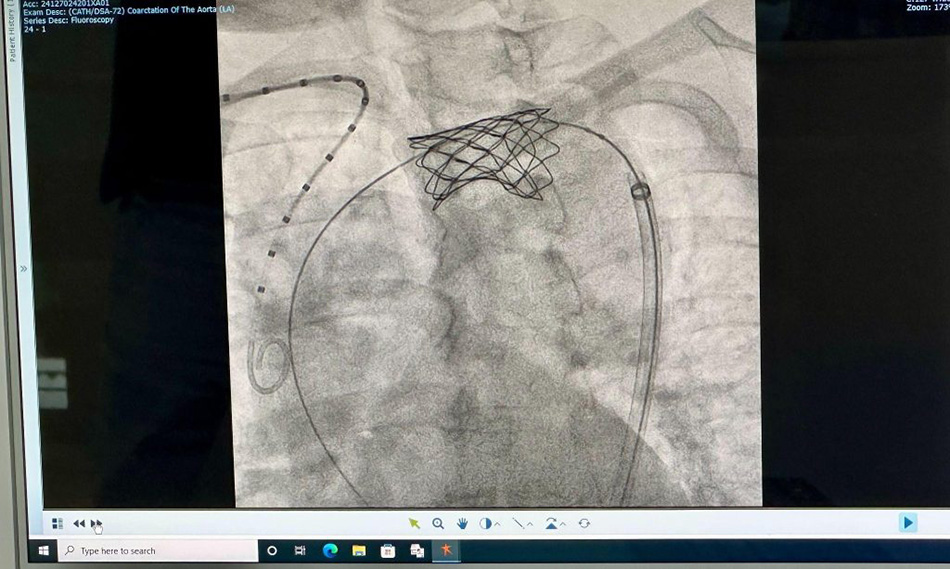

The stent placement for Ms L. on November 26th proceeded smoothly. Dr Ho Minh Tuan performed the balloon dilation and stent placement with the assistance of a Digital Subtraction Angiography (DSA) system. The procedure was successfully completed in just 60 minutes, and the patient remained fully awake throughout.

The image of the aortic stent captured after successful placement